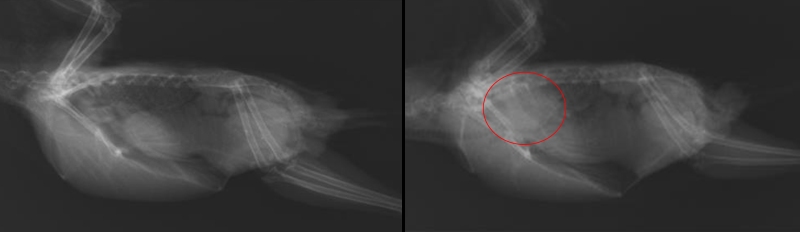

甲状腺腫

ヨウ素不足から甲状腺が腫れ、その結果、呼吸器や消化器、循環器などを圧迫する病気です(図2)。血を吐いて突然死してしまうことも多いです。症状としては、ヒューヒューと呼吸音がする、嘴(くちばし)を開けて苦しそうに呼吸するなどがみられます。

予防としては、ヨウ素をしっかりと含んだ信頼できるサプリメントを与えること、ヨウ素の吸収を阻害するブロッコリーなどのアブラナ科植物を多給しないことが有効です。